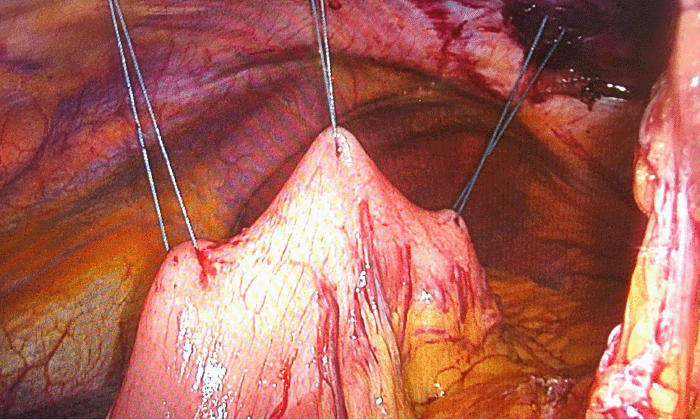

Given the increased gastric mobility and ligament laxity associated with advanced age, a prophylactic gastropexy was performed using three non-absorbable seromuscular sutures placed intracorporeally along the greater curvature (Figure 4). Suture ends were passed through the abdominal wall and tied.

Figure 4. Laparoscopic View of Gastropexy. Published with Permission

Operation was achieved with three non-absorbable seromuscular sutures placed intracorporeally along the greater curvature of the stomach.